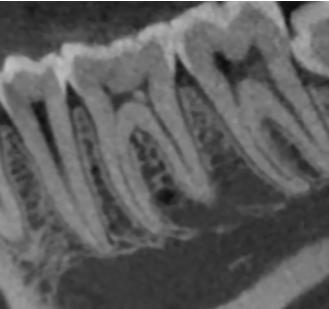

a. Observar radiográficamente las características anatómicas y dimensionales de los caninos superiores e inferiores respecto a dientes adyacentes (Figura 11).

b. Identificar radiográficamente la posición en que se encuentra el canino, respecto a los dientes adyacentes (Figura 12).

A partir de los 8 años, se puede observar radiográficamente el inicio de la reabsorción del canino deciduo (Figura 17).

El seguimiento del trayecto canino con un estudio radiográfico postero anterior, lateral de cráneo y ortopantomográfico, a partir de la edad señalada anteriormente, también es una herramienta efectiva que permite obtener un diagnóstico inicial, donde podrá observarse si se ha iniciado la reabsorción radicular del canino deciduo e identificar qué